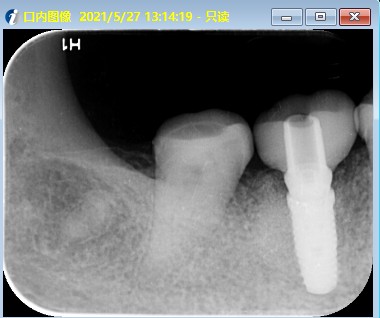

患者右下后牙根管治疗十年后咬合不适,x片显示近中根尖阴影较大,根折,患牙不能保留,患者非常焦虑拔牙,更怕种植牙,要求拔牙后即刻种植,通过CBCT检查,确定剩余骨量足够多,可以即拔即种植;患者知情同意下,完成即拔即种,四个月后CEREC数字化扫描,当天完成了牙冠修复,同时邻牙也完成嵌体修复!有图有真相。